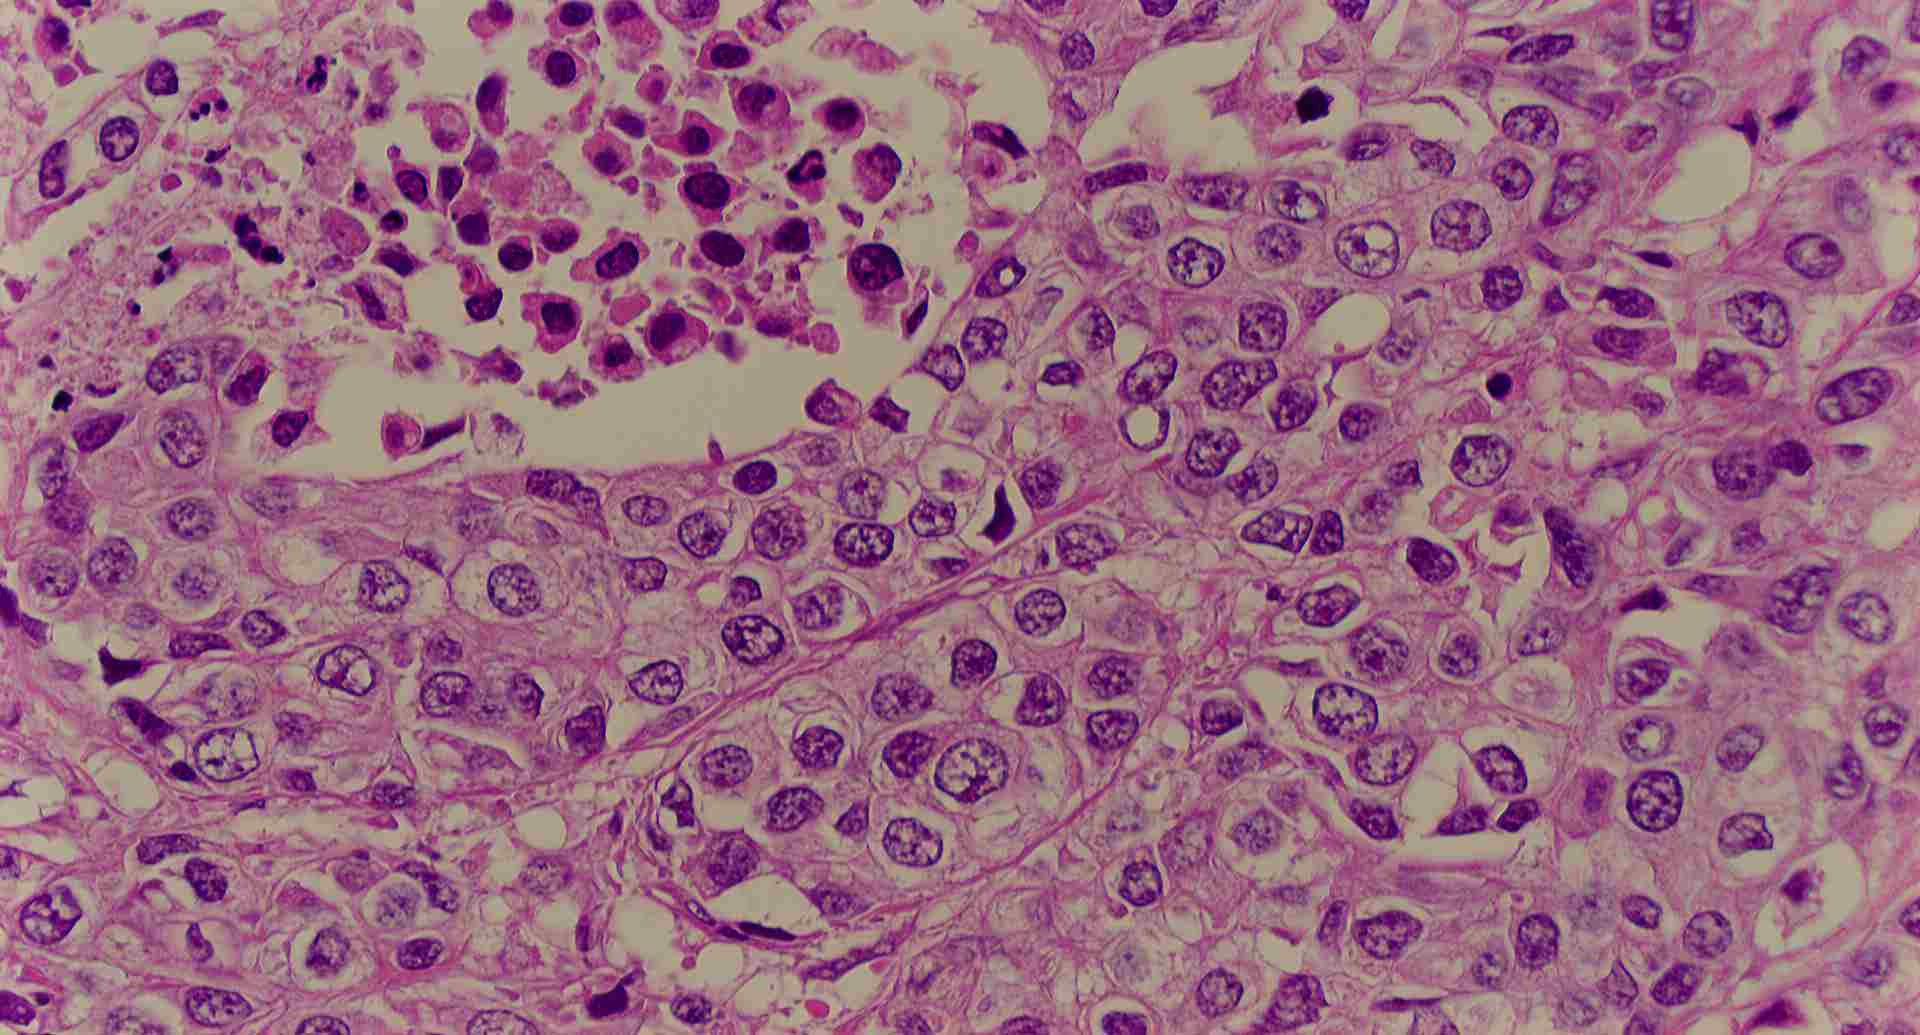

標本8

標本8の説明